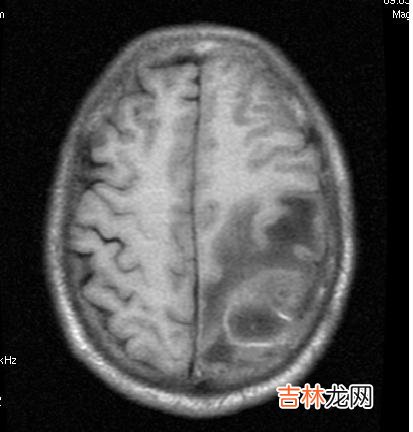

眼底检查,脑脓肿的患者视乳头可出现水肿 。颅脑ct扫描或mri(磁共振)检查,可显示脓肿的大小、位置、数目及脑室受压等 。在乳突手术时,用针头穿刺吸脓,可明确诊断 。如脓肿可能性很大,神经外科医生可在附近钻孔,直接穿刺脓肿放脓 。